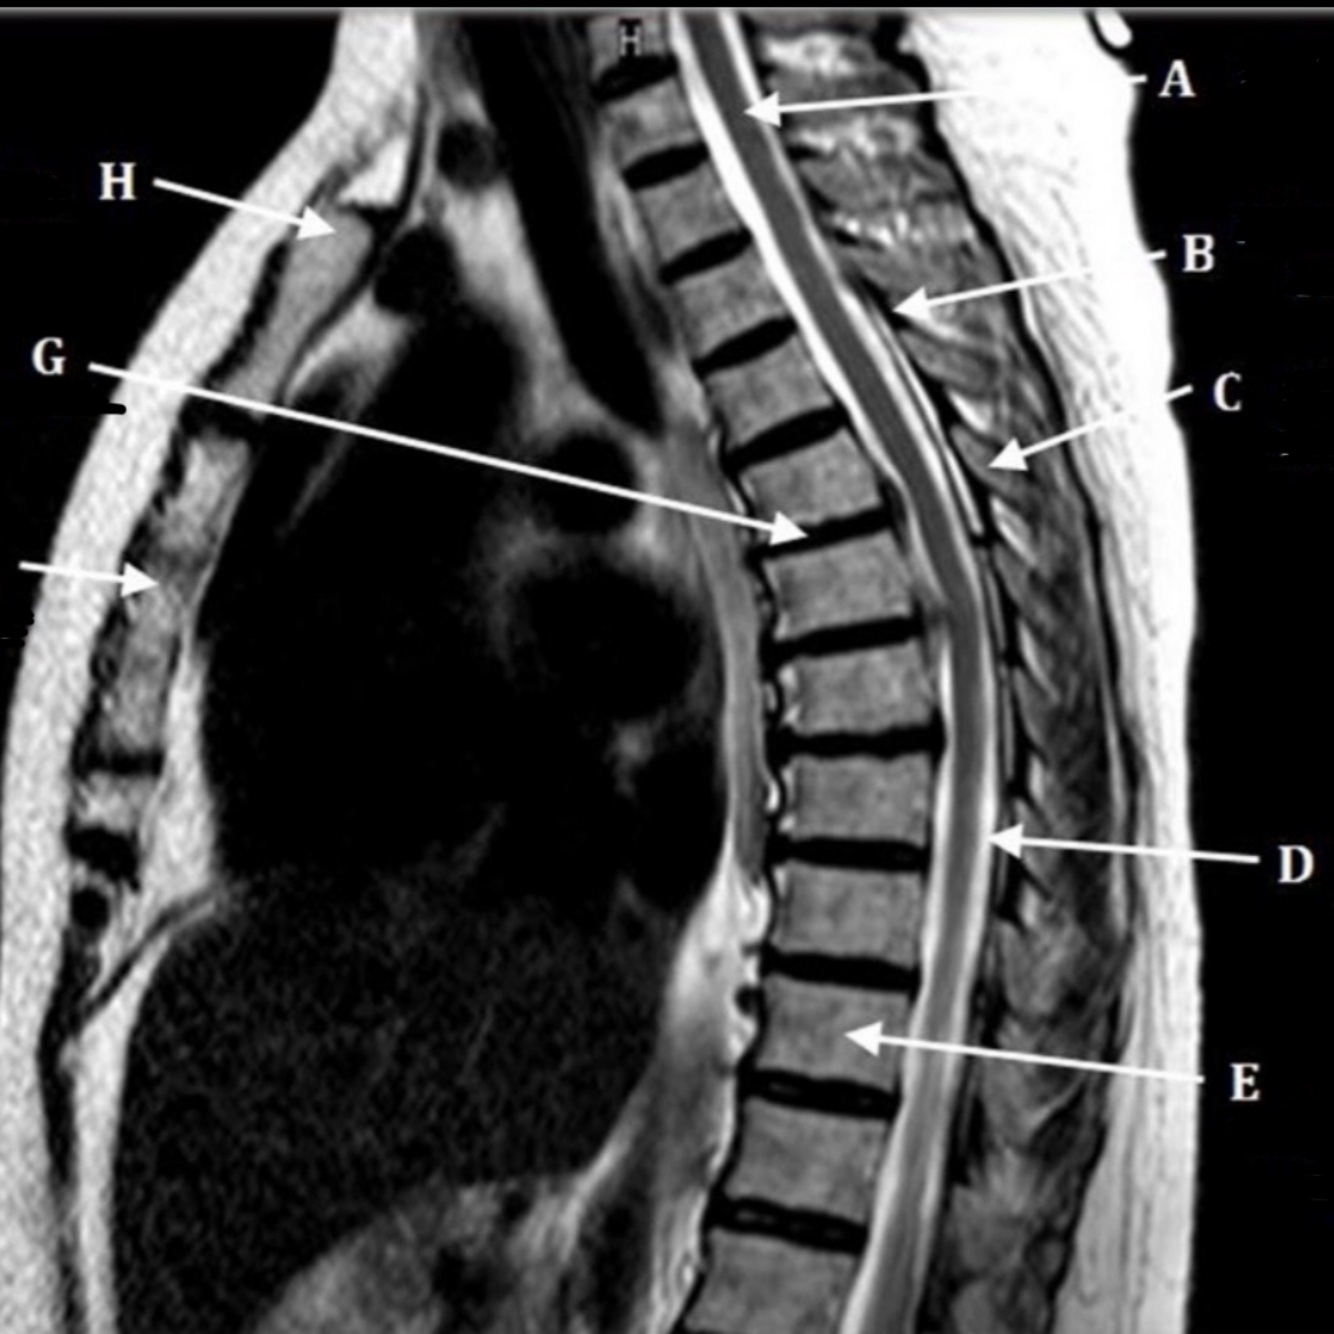

55

What is letter A?

CEREBELLUM

56

What is letter B?

SPINAL CORD

57

What is letter C?

CSF

58

What is letter D?

SPINOUS PROCESS

59

What is letter E?

S1 VERTEBRAL BODY

60

What is letter F?

INTERVERTEBRAL DISK SPACE

61

What is letter G?

12TH THORACIC VERTEBRAE

62

What is letter H?

7TH THORACIC VERTEBRAE

63

What is letter J?

SUPRASTERNAL NOTCH

64

What is letter K?

3RD CERVICAL VERTEBRAE

65

What is letter L?

PONS